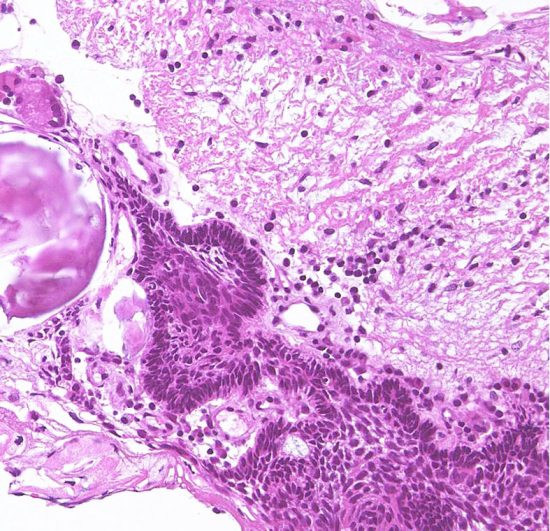

Xanthogranulomatous part in an adamantinomatous craniopharyngioma showing cholesterol clefts (upper left) surrounded by collagen tissue, dense macrophage infiltration, and lymphatic infiltrates (upper right)